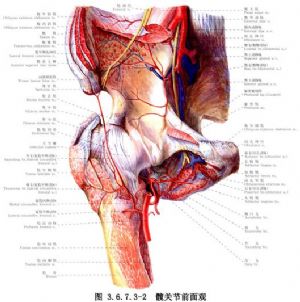

手術相關解剖見下圖(圖3.6.7.3-1~3.6.7.3-4)。